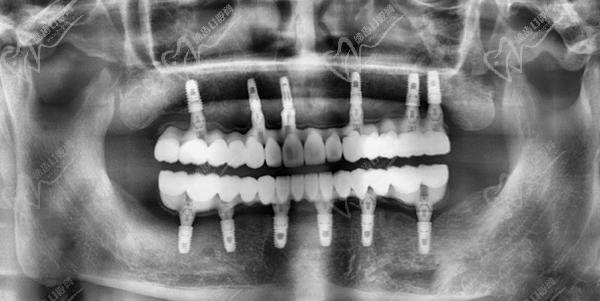

廣州曙光美云口腔醫(yī)院采用的全口即刻種植牙技術(shù),也被稱(chēng)為"ALL-ON-4"或"ALL-ON-6"種植技術(shù),是目前種植牙領(lǐng)域先 進(jìn)的技術(shù)之一。該技術(shù)可以在當(dāng)天完成全口缺牙的修復(fù),并能長(zhǎng)期使用,具有以下優(yōu)勢(shì):

廣州曙光美云口腔醫(yī)院全口即刻種植牙采用4顆或6顆種植體植入牙床,在上面安裝基臺(tái)并連接,后安裝"拱形連橋"牙冠。這種方式不會(huì)影響植體和牙槽骨的骨結(jié)合,而且能獲得與傳統(tǒng)延期種植相同的骨結(jié)合效 果。同時(shí),它還能避免增加骨粉膜重建和修復(fù)的過(guò)程,大大縮短了種植時(shí)間,減輕了患者的痛苦。簡(jiǎn)單說(shuō)就是: